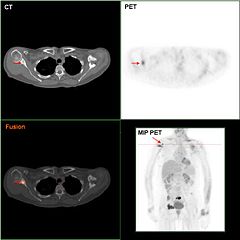

The objective of the project is to Predict whether the tumor is cancerous (Malignant) type or non-cancerous (Benign).

Plotted Model performance graph of different ML algorithms and, Concluded prediction accuracy of 99% with Logistic Regression classifier.